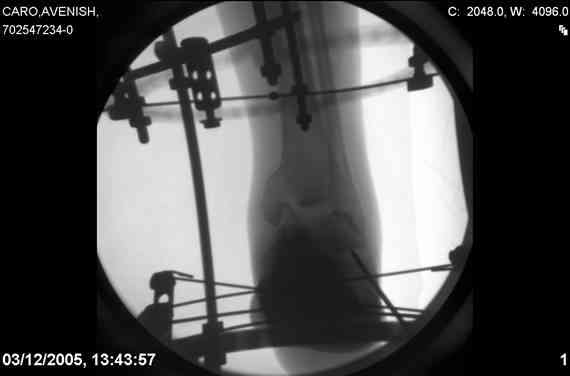

ya by popytalsya sobrat talus anatomichno,seichas pozdno operirovat iz za oteka,po etomy distrakziya apparatom budet optmalna.Posyalu vam podobyai moi sluchai.

14 years old girl

Fall from height ( 3rd floor)

Compressed fractures of L1-L2

Fx of orbital bone

Mark, судя по снимкам в день поступления произведен А.В.Ф., а остеосинтез ч-з какое время произведен?, остеосинтез произвели открытым способом?( на снимке п/о рубцы).

aparat postavlen v den postupleniya,rastaynuli, vpravili zakryto naskolko vozmoghno, a kogda otek spal sdelali otkrytoe vpravlenie.Teryat tut nechego, moghno tolko uluchshit.